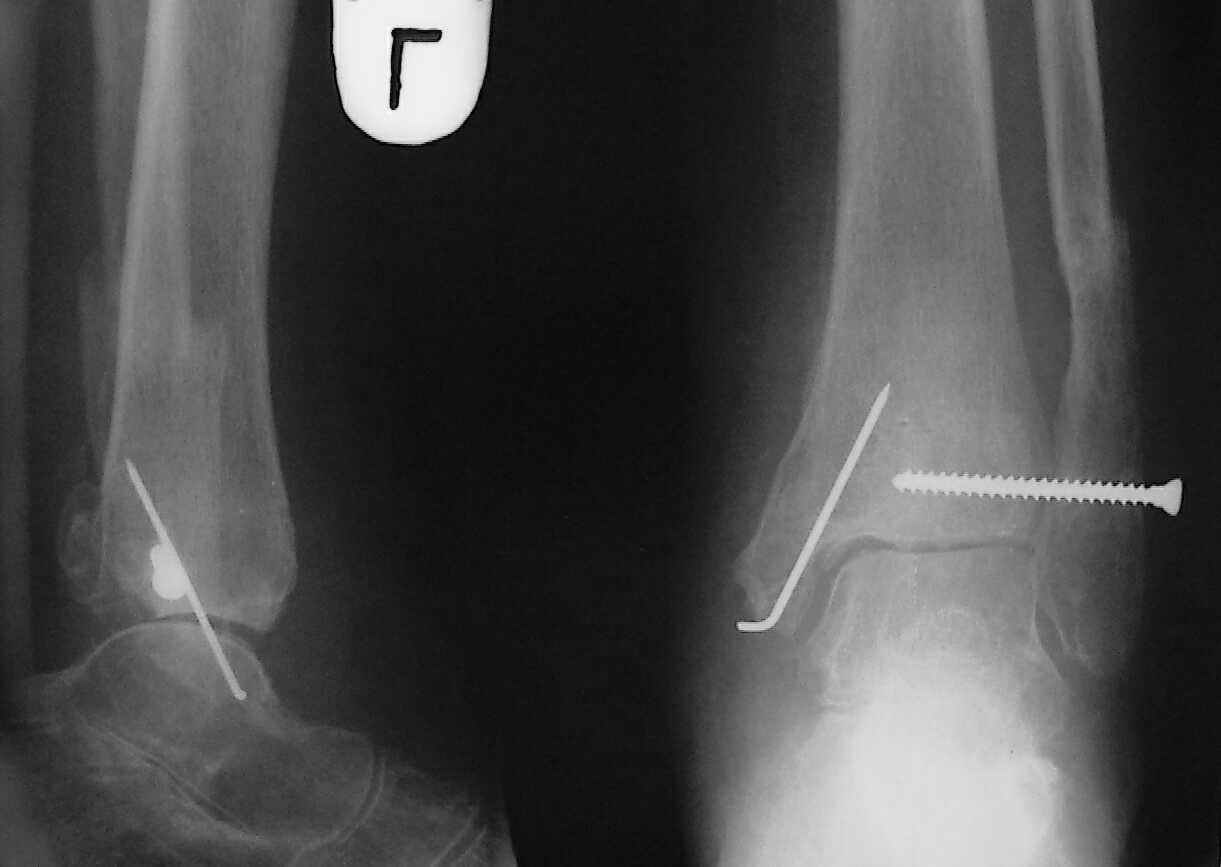

Больная 1936 г.,травма 15 ноября 2003,закрытый трехлодыжечный перелом г/стопного сустава, сахарный диабет.

При поступлении - закрытая репозиция, повторная в связи с большим отеком через неделю, подготовлена к остеосинтезу в первых числах декабря. Заживление без осложнений. Циркулярный гипс - 7 недель, снят,часть спиц удалено 20 февраля т.к.пальпировались под кожей, постепенная нагрузка, проблем нет до середины апреля когда появильсь боли с мед. стороны сустава и локалная гиперемия ( трактовалась как флеботромбоз). Повторное поступление 15 апреля - усиление болей,пов. температура, локально выраженная гиперемия.Локально выделений нет. На RTG - деструкция в области мед лодыжки и заднего края. Сахар крови умеренно повышен. Как трактовать проблему, какой диагноз и тактика лечения? Заранее спасибо, Владимир.